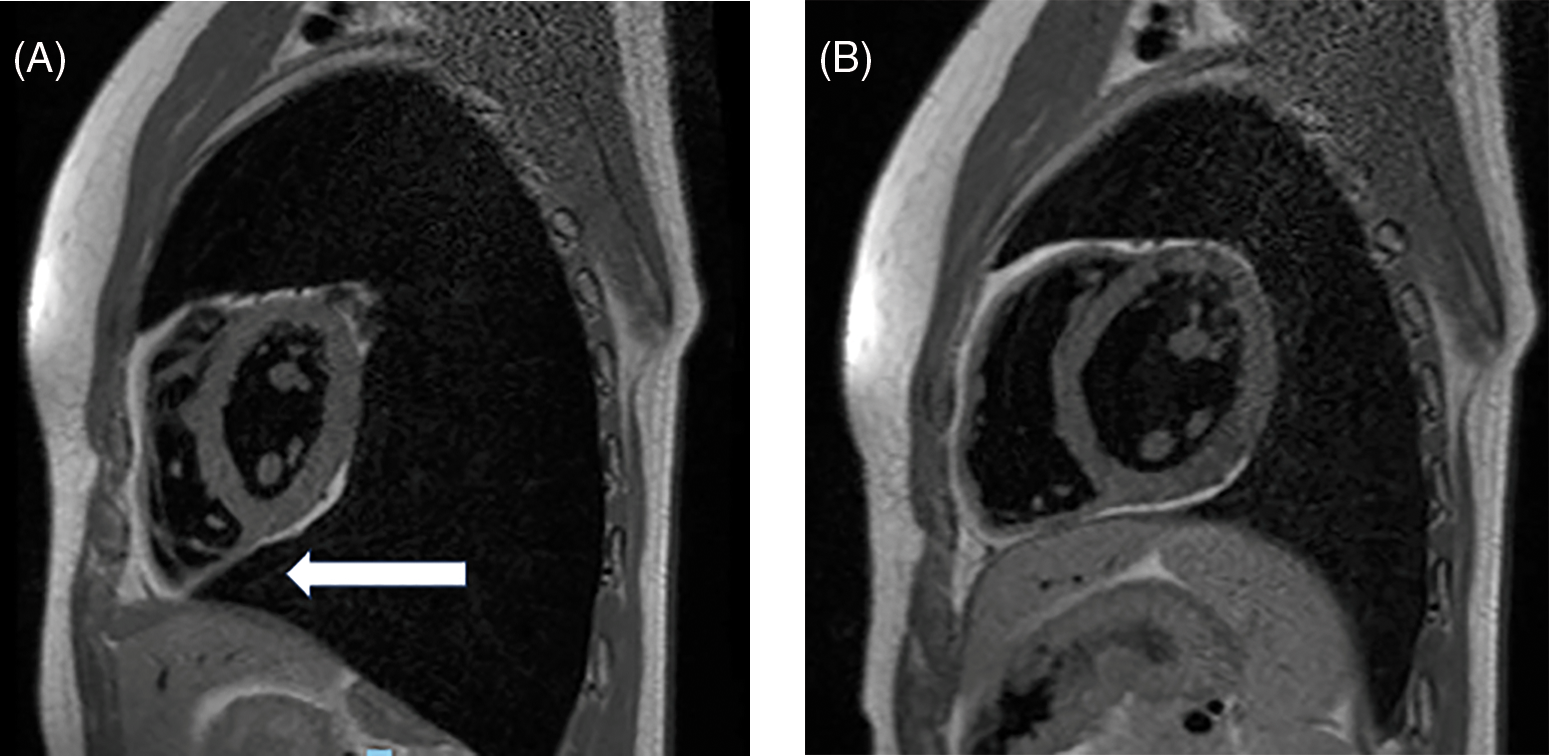

See Figs. 1–3 for a description of the diagnostic criteria.

Figure 3: Cardiac magnetic resonance (sagittal views, T 1 weighed images) during inspiration (panel A) and expiration (panel B) displaying the lung interposing under the heart and extending between the cardiac inferior surface and the left diaphragm (see white arrow. Previously unpublished images belonging to the authors)